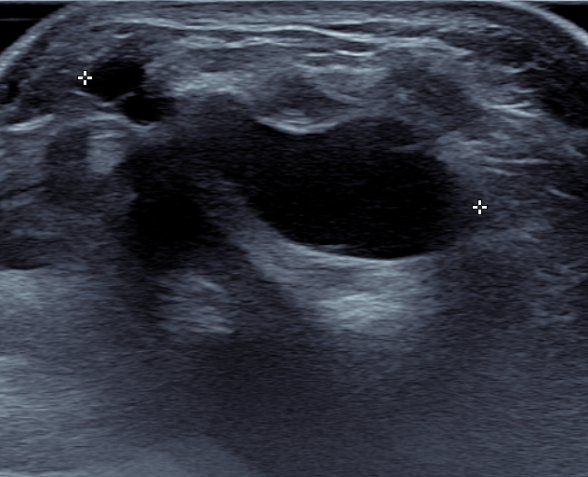

Ultrasound

Volar ganglion with radial artery superficial to ganglion